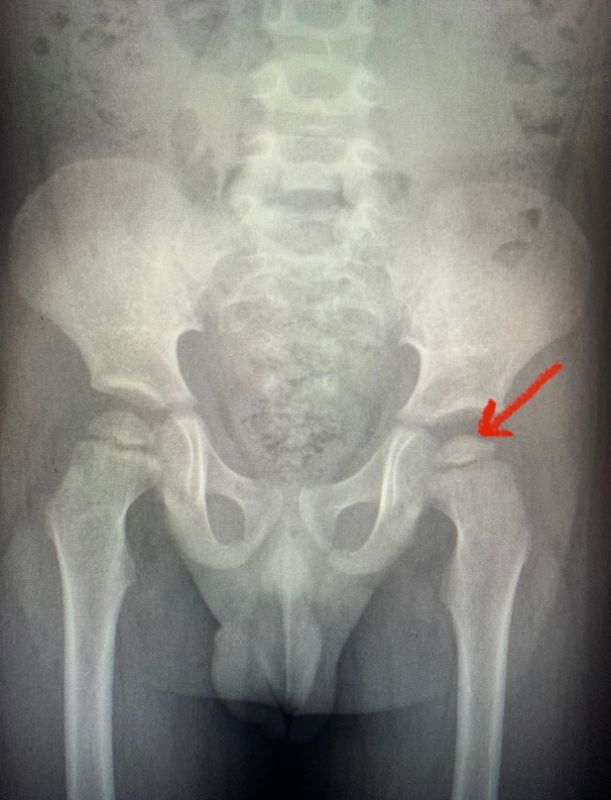

Малышу из Воронежа поставили диагноз «болезнь Пертеса слева», при которой постепенно отмирает головка бедренной кости, после жалоб на боль в ноге, рассказали медики областной детской больницы № 2.

В больнице малышу сделали рентген, который подтвердил серьёзный недуг. Другие анализы ребёнка были в норме. Малыша срочно госпитализировали в отделение ортопедии.